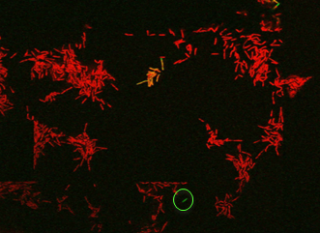

Live imaging snapshot of Mycobacterial cells treated with the front-line antibiotic rifampicin. The green GFP cell is a live persister cell which grows back upon antibiotic removal. The red cells are dead (PI stained).